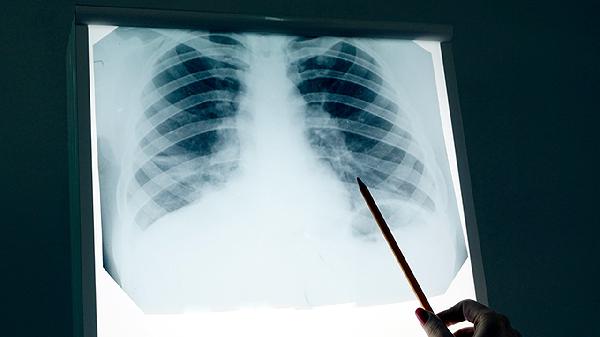

术后短期内出现的磨玻璃结节常见于局部组织修复过程中的炎性反应,尤其是胸腔镜手术后的胸膜粘连或肺泡出血吸收期。这类结节通常边缘模糊、密度均匀,随访中可能逐渐缩小或消失。术后复查的低剂量CT若显示结节形态规则、无血管集束征或空泡征等恶性特征,更倾向良性病变可能。对于存在高危因素如长期吸烟史或家族肿瘤史的患者,需警惕多原发肺癌可能,此时结节多表现为持续存在或缓慢增长。

当磨玻璃结节呈现分叶状、毛刺征等典型恶性征象,或随访中体积增大、实性成分增加时,需考虑肿瘤复发或第二原发癌可能。微浸润性腺癌本身复发概率较低,但若初次手术切除不彻底,残留的非典型腺瘤样增生可能进展为浸润灶。病理亚型如贴壁型为主的肿瘤更易出现多灶性生长,需通过PET-CT或穿刺活检明确性质。